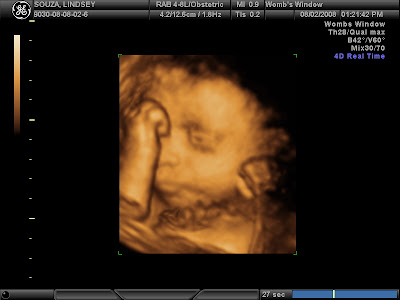

He was asleep when she started the scan but only took a moment to wake right up. And begin poking and jabbing and kicking at the pressure of the ultrasound wand thing. After about 30-35 minutes of being in perfect position for pictures and us seeing his face, he promptly rolled over to face my back then she REALLY had to work to get shots of him, including asking me to eat candy (Travis got a piece too). He was set on being stubborn though and wouldn't flip back over so after about 10 minutes of seeing what we could like he was, we called it a day. It was only supposed to be 30 minutes so I had no complaints. He kept his hands up around his face. Sometimes over it, sometimes just in front of it. Occasionally a foot would pop up there also. As you'll see in the pictures, he would OPEN HIS EYES some too. Travis really liked that. All in all, we were all amazed and it was worth every cent to do it. I wanted to put some of the dvd on here, but ummm, video conversion isn't my strong point and I've already got 1 email asking where are the pictures, so I'm just going to put them up here for now! Here are my favorites:

A little smile